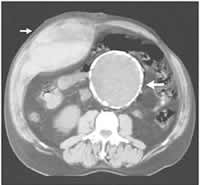

(2)B超或CT掃描:可發現腫塊位於腹壁腹直肌內,密度偏低,界線清晰,與腹腔不相。